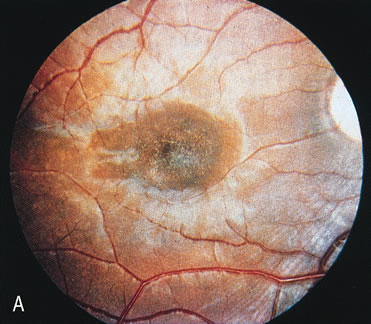

In retinitis pigmentosa (RP), the pigment abnormalities of atrophy, migration, and clumping are made apparent by transmitted hyperfluorescence and blocked hypofluorescence (Fig. 1A). Patients who have very minimal pigmentary alterations (pauci pigmentary RP) or no pigment abnormalities (RP sine pigmento) may show the abnormalities on fluorescien angiography (FA). It is uncommon to see choriocapillaris atrophy except in the late stages. This finding corresponds to the histopathology, which shows that the earliest abnormalities are in the photoreceptors and that the choroid is normal.1

Dye leakage in RP may occur from the retinal vessels or at the level of the retinal pigment epithelium (Fig. 1B).2–4 The leakage may be seen in the macula and posterior pole, along the vascular arcades in the distribution of the radial peripapillary capillaries, and in the periphery (where an exudative vasculopathy resembling Coats' disease is suggested).